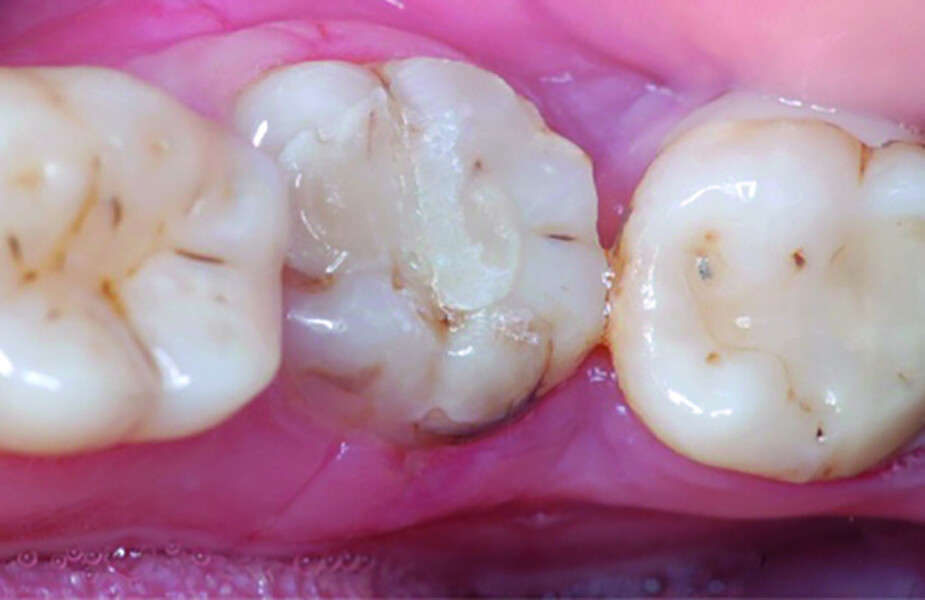

Fig. 13: Pulp chamber floor perforation, tooth cleaned.